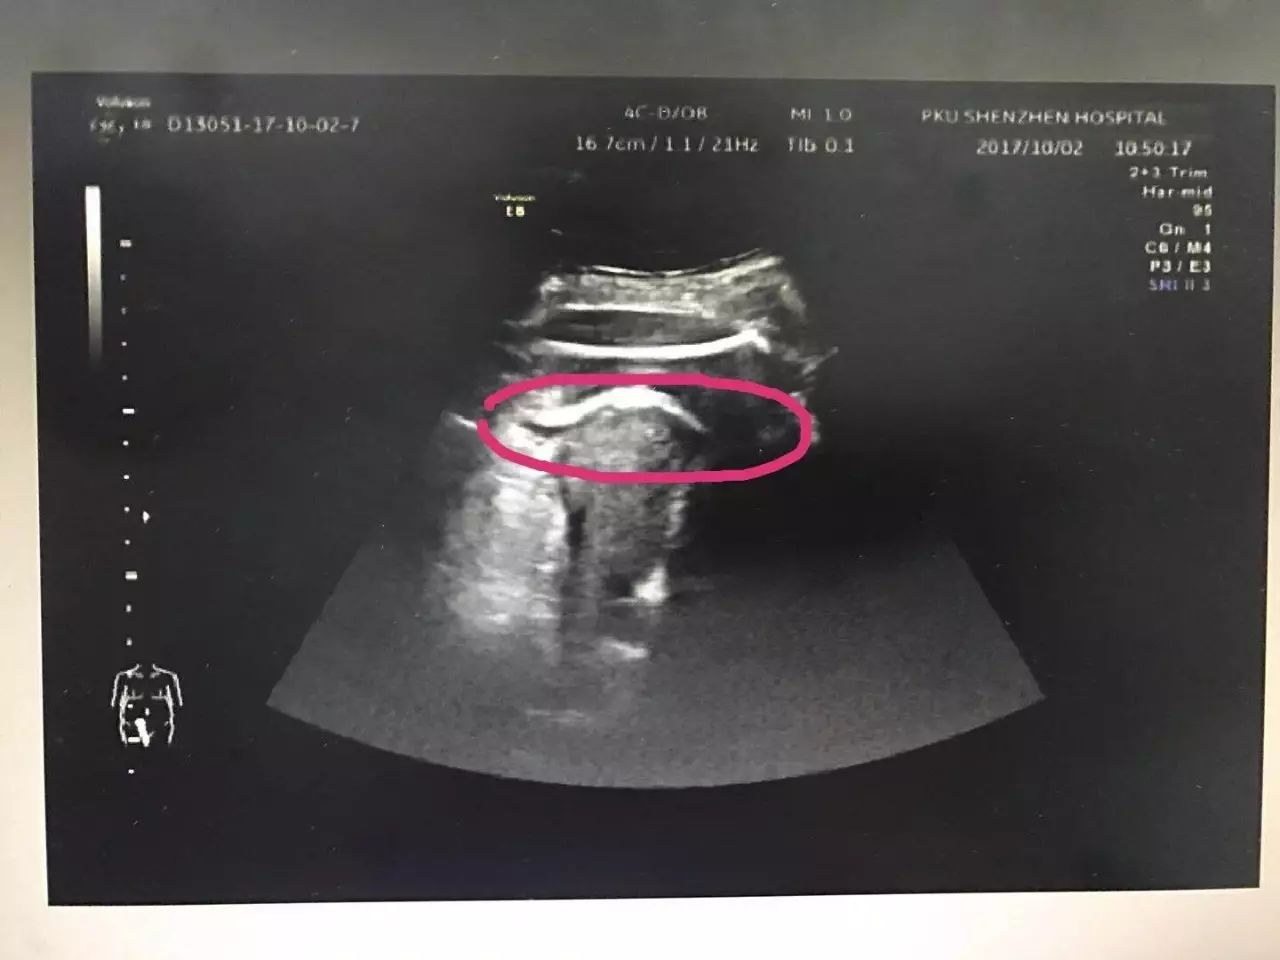

△红色圆圈处是胎儿的腿,已经伸到子宫壁外

◎凭借有限病史及B超检查,医生快速作出诊断:考虑疤痕子宫破裂。